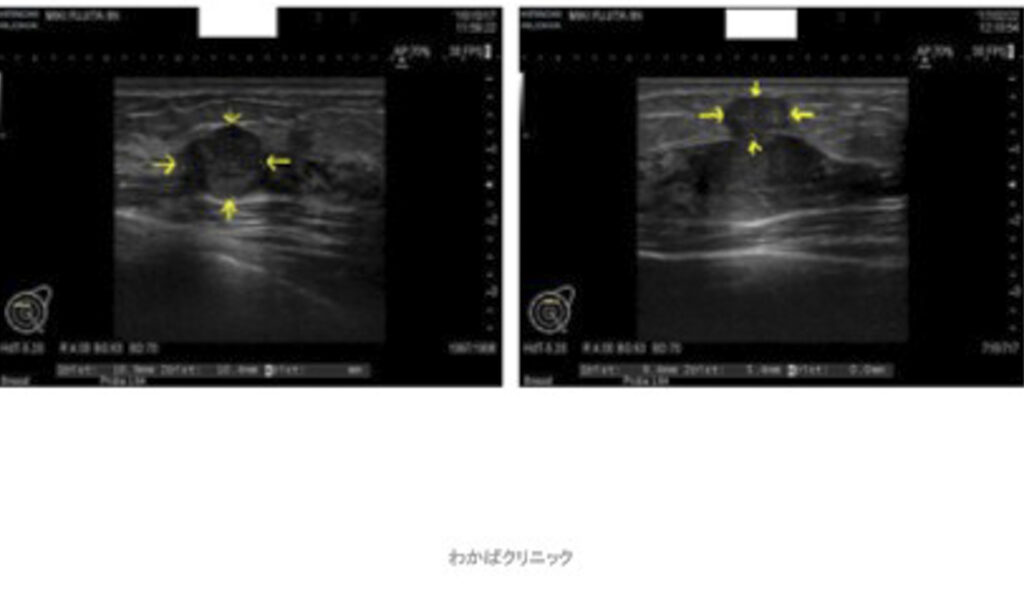

- 西洋医学的な効果判定(必ず必要です)

- CT・MRI・超音波検査 他